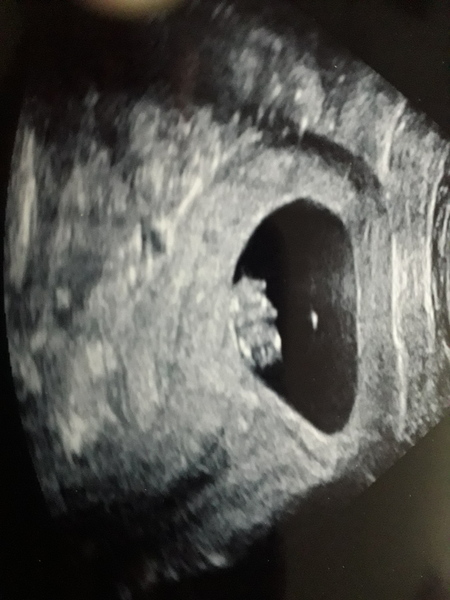

northernsquirrel · 26/01/2021 19:52

Had an early pregnancy scan done for peace of mind, all looks good 😊 I'm 9 weeks today x

Congrats on the positive scan @northernsquirrel great news!

@northernsquirrel super news! Looks like a cute little gummy bear so cute Grin

Lovely scan @northernsquirrel!

Thanks everyone for liking my scan, still feels a bit surreal at times x